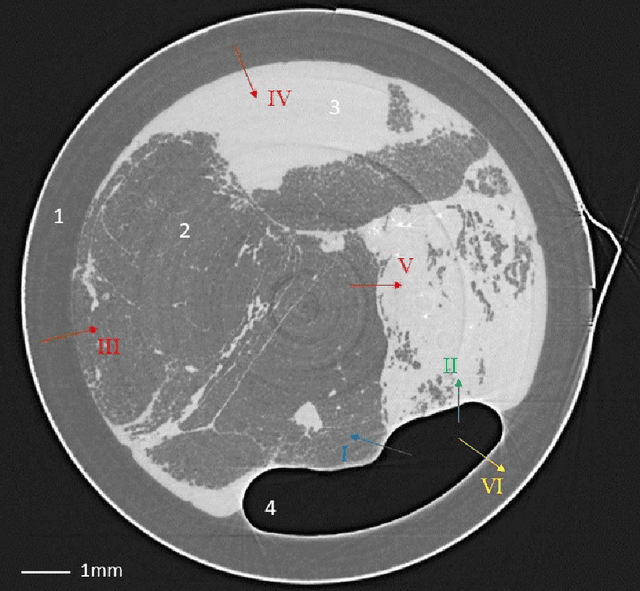

Abstract:Propagation-based phase-contrast X-ray imaging (PB-PCXI) generates image contrast by utilizing sample-imposed phase-shifts. This has proven useful when imaging weakly-attenuating samples, as conventional attenuation-based imaging does not always provide adequate contrast. We present a PB-PCXI algorithm capable of extracting the X-ray attenuation, $\beta$, and refraction, $\delta$, components of the complex refractive index of distinct materials within an unknown sample. The method involves curve-fitting an error-function-based model to a phase-retrieved interface in a PB-PCXI tomographic reconstruction, which is obtained when Paganin-type phase-retrieval is applied with incorrect values of $\delta$ and $\beta$. The fit parameters can then be used to calculate true $\delta$ and $\beta$ values for composite materials. This approach requires no a priori sample information, making it broadly applicable. Our PB-PCXI reconstruction is single distance, requiring only one exposure per tomographic angle, which is important for radiosensitive samples. We apply this approach to a breast-tissue sample, recovering the refraction component, $\delta$, with 0.6 - 2.4\% accuracy compared to theoretical values.